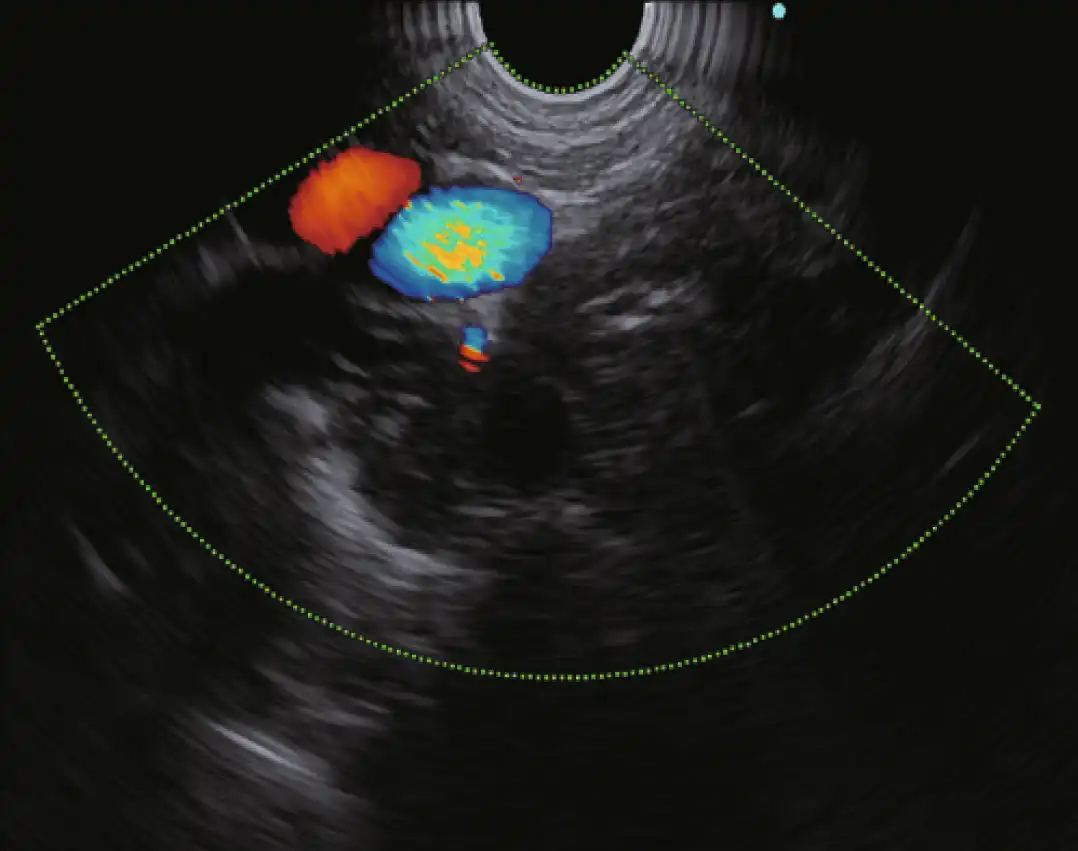

多普勒模式

EU-ME3 提供三种基本的多普勒模式,以更清楚地分辨血流--彩色血流、能量血流和脉冲波多普勒(PWD)。多普勒模式可用于支持更安全的手术,使病人和医生都受益。

除了三种基本的多普勒模式外,EU-ME3还具有H-Flow模式。H-Flow是一种更敏感的多普勒模式,可显示定向血流,且花纹较少。它对回声内窥镜尖端周围的小血管成像特别有用。

彩色流 能量流

脉冲波多普勒 H-Flow